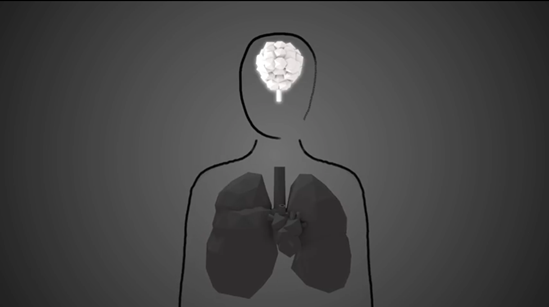

Air pollution is a major environmental health threat and one of the main risk factors for noncommunicable diseases. Globally, air pollution is responsible for about 7 million premature deaths per year due to ischemic heart disease, stroke, chronic obstructive pulmonary disease and lung cancer, but also from acute lower respiratory tract infections. Further, a growing and consistent body of evidence shows that additional air pollution health effects include preterm and low birth weight, exacerbation and onset of asthma, as well as cognitive and neurological impairment.